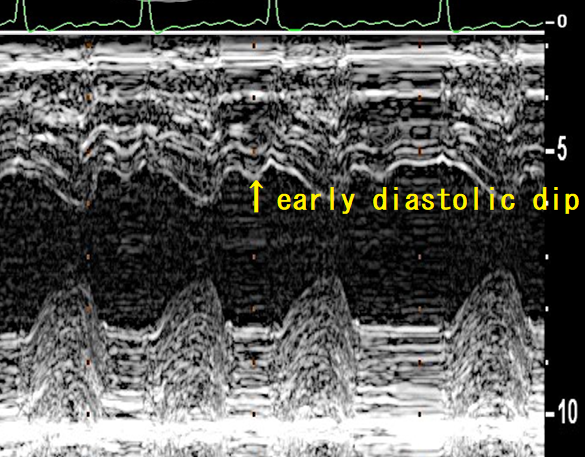

傍胸骨よりのM-modeでは拡張早期に心室中隔が素早く動くearly diastolic dipがみられ、拡張期の右室圧と左室圧の関係を反映した現象である。